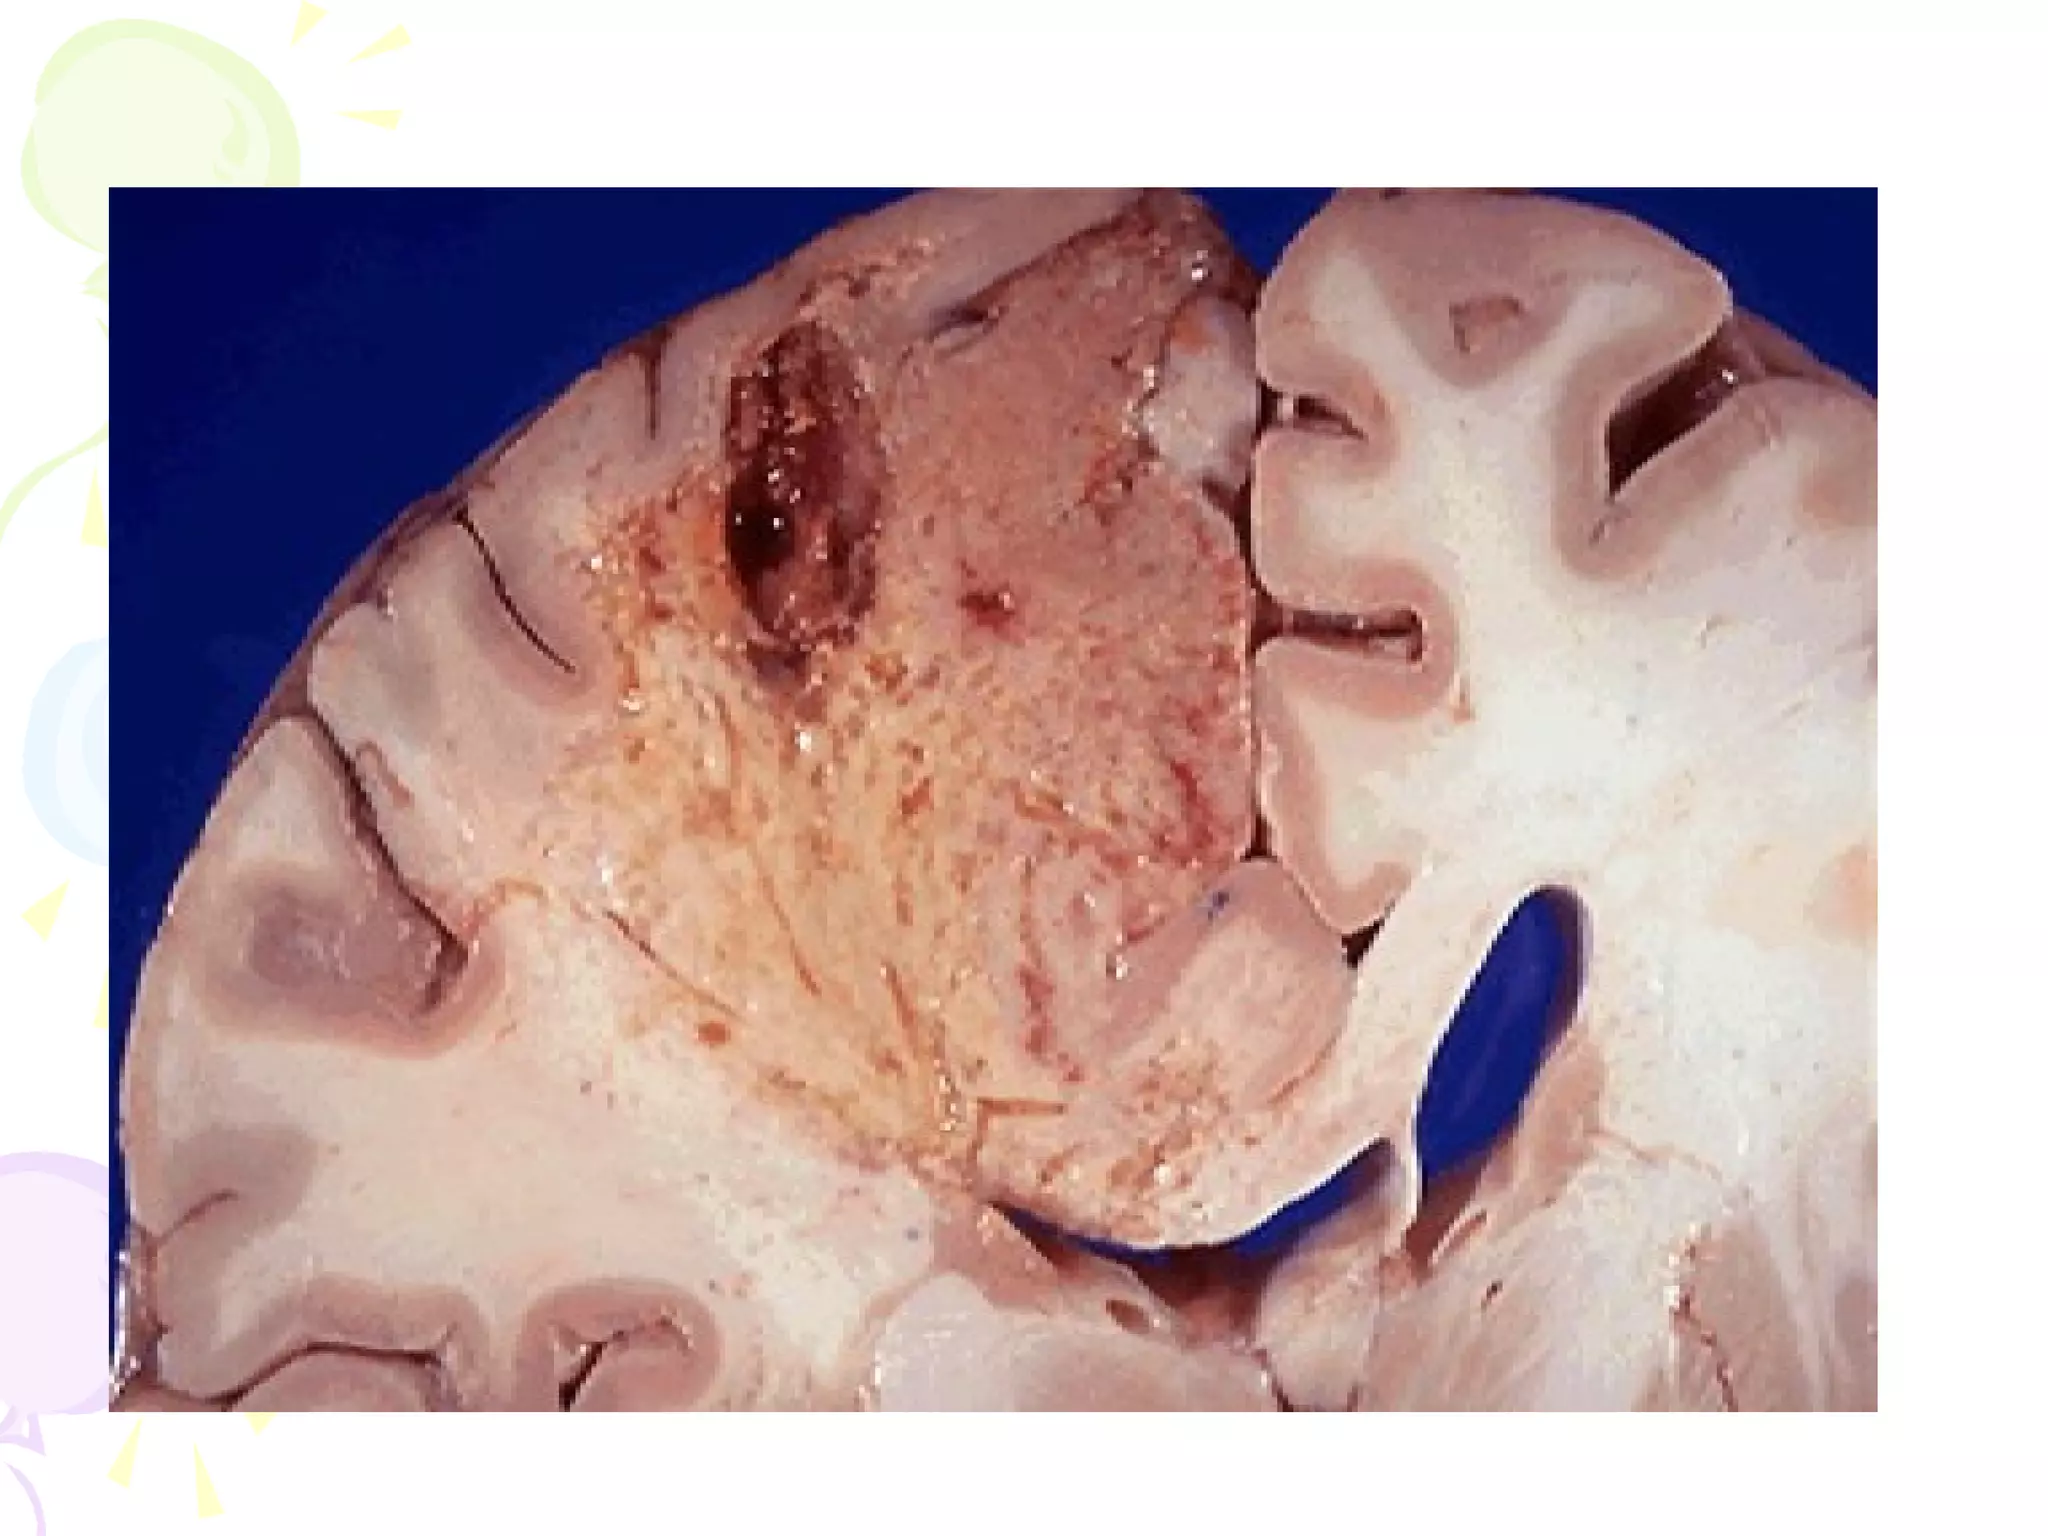

• Liquefactive Necrosis

- focal bacterial (or fungal) infections

– accumulation of inflammatory

cells

- hypoxic death of cells within CNS

LIQUEFACTIVE NECROSIS

• (* "colliquative necrosis" in Europe): When

the cells die, they are rapidly destroyed by

lysosomal enzymes, either their own or

those from neutrophilic leukocytes

• The tissue becomes liquid viscous mass

• Material is creamy yellow in color

• Seen in ischemia of brain, abscess

Normal brain   Liquefactive necrosis